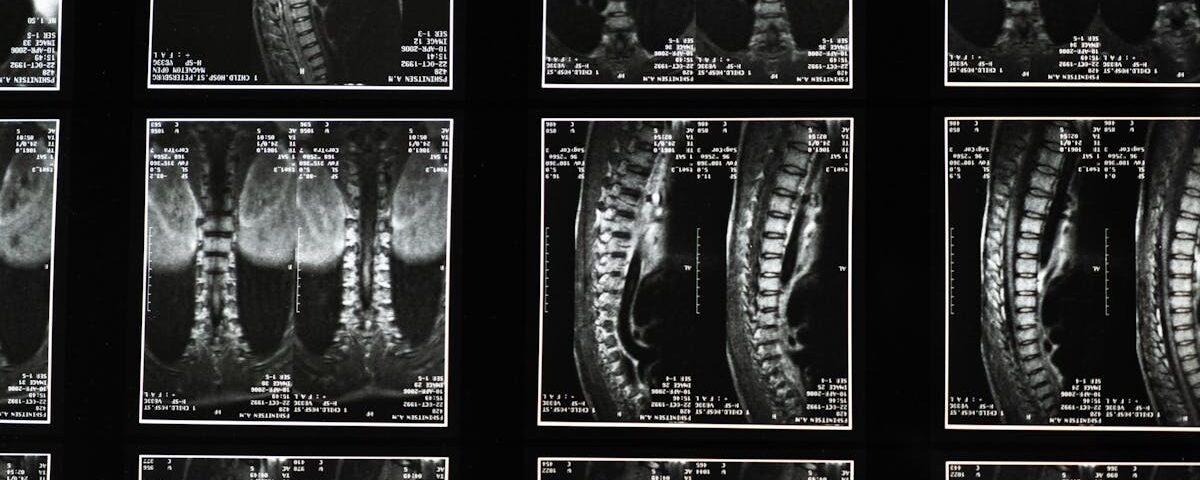

Quels examens permettent de diagnostiquer un pincement discal?

Une IRM ou une radiographie est souvent utilisée pour confirmer le diagnostic d’un pincement discal ou d’un disque écrasé.

Quels examens sont nécessaires avant de commencer un traitement de décompression pour un disque écrasé?

Une IRM ou une radiographie est souvent recommandée pour évaluer l’état de la colonne vertébrale.